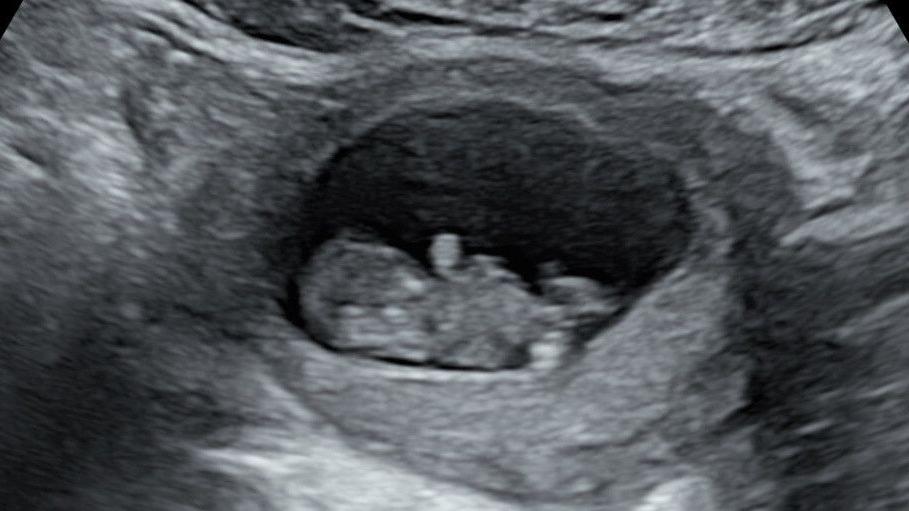

Early scans of baby Hudson were initially reassuring to his mother Rhiannon

In October last year, she found out she was pregnant again and this time was reassured with some early scans.

But then came the 20-week scan, which revealed the baby boy - who the couple called Hudson - had a severe form of hypoplastic left heart syndrome, external.

"There was no way forward," she says, and Hudson was stillborn in March at 22 weeks.